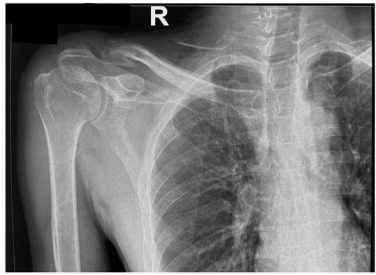

Under general anesthesia, the patient was positioned in the lateral decubitus position. Intraoperative localization of the K-wire fragments was achieved using fluoroscopic guidance, correlating with pre-operative CT findings. A single curvilinear incision was made over the posterior cervical region and extended anteriorly toward the supraclavicular fossa (Fig. 3a).

Figure 3: Intraoperative photographs showing the skin incision (a) and retrieval of the two K-wire fragments (b-d).

Dissection was carefully performed in two anatomical planes around the trapezius muscle. The first K-wire fragment was identified anterior to the trapezius within the supraclavicular region. After blunt and sharp dissection through the platysma and fascia, the wire (8 cm length) was successfully retrieved (Fig. 3b). Dissection then continued posterior to the trapezius, where the second K-wire fragment (7 cm length) was located in the paraspinal musculature and removed without difficulty (Fig. 3c and d). In the same operative session, a separate incision was made over the acromion process to remove the tension band wiring from the acromioclavicular joint. The lateral clavicle fracture was found to be malunited, but as the patient was asymptomatic, no further intervention was performed. Both surgical sites were irrigated thoroughly and closed in layers. Post-operative radiographs confirmed complete removal of hardware (Fig. 4). The patient recovered uneventfully, with complete resolution of symptoms by the 1-month follow-up. At 3 months, he remained pain-free with a full, pain-free range of motion at the shoulder and cervical spine.

Figure 4: Post-operative radiograph confirming complete removal of the migrated K-wire fragments and the previously placed tension band wiring from the acromioclavicular joint.